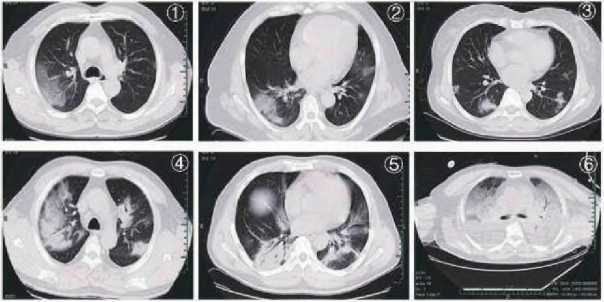

Характерные признаки COVID-19 на снимках КТ:

Рис. 1, Рис. 2: очаговые субплевральные фокусы уплотнения по типу «матового стекла»;

Рис. 3: узлы и очаговая экссудация;

Рис. 4, Рис. 5: многоочаговые уплотнения на пораженных участках;

Рис. 6: диффузные уплотнения, «белое лёгкое».